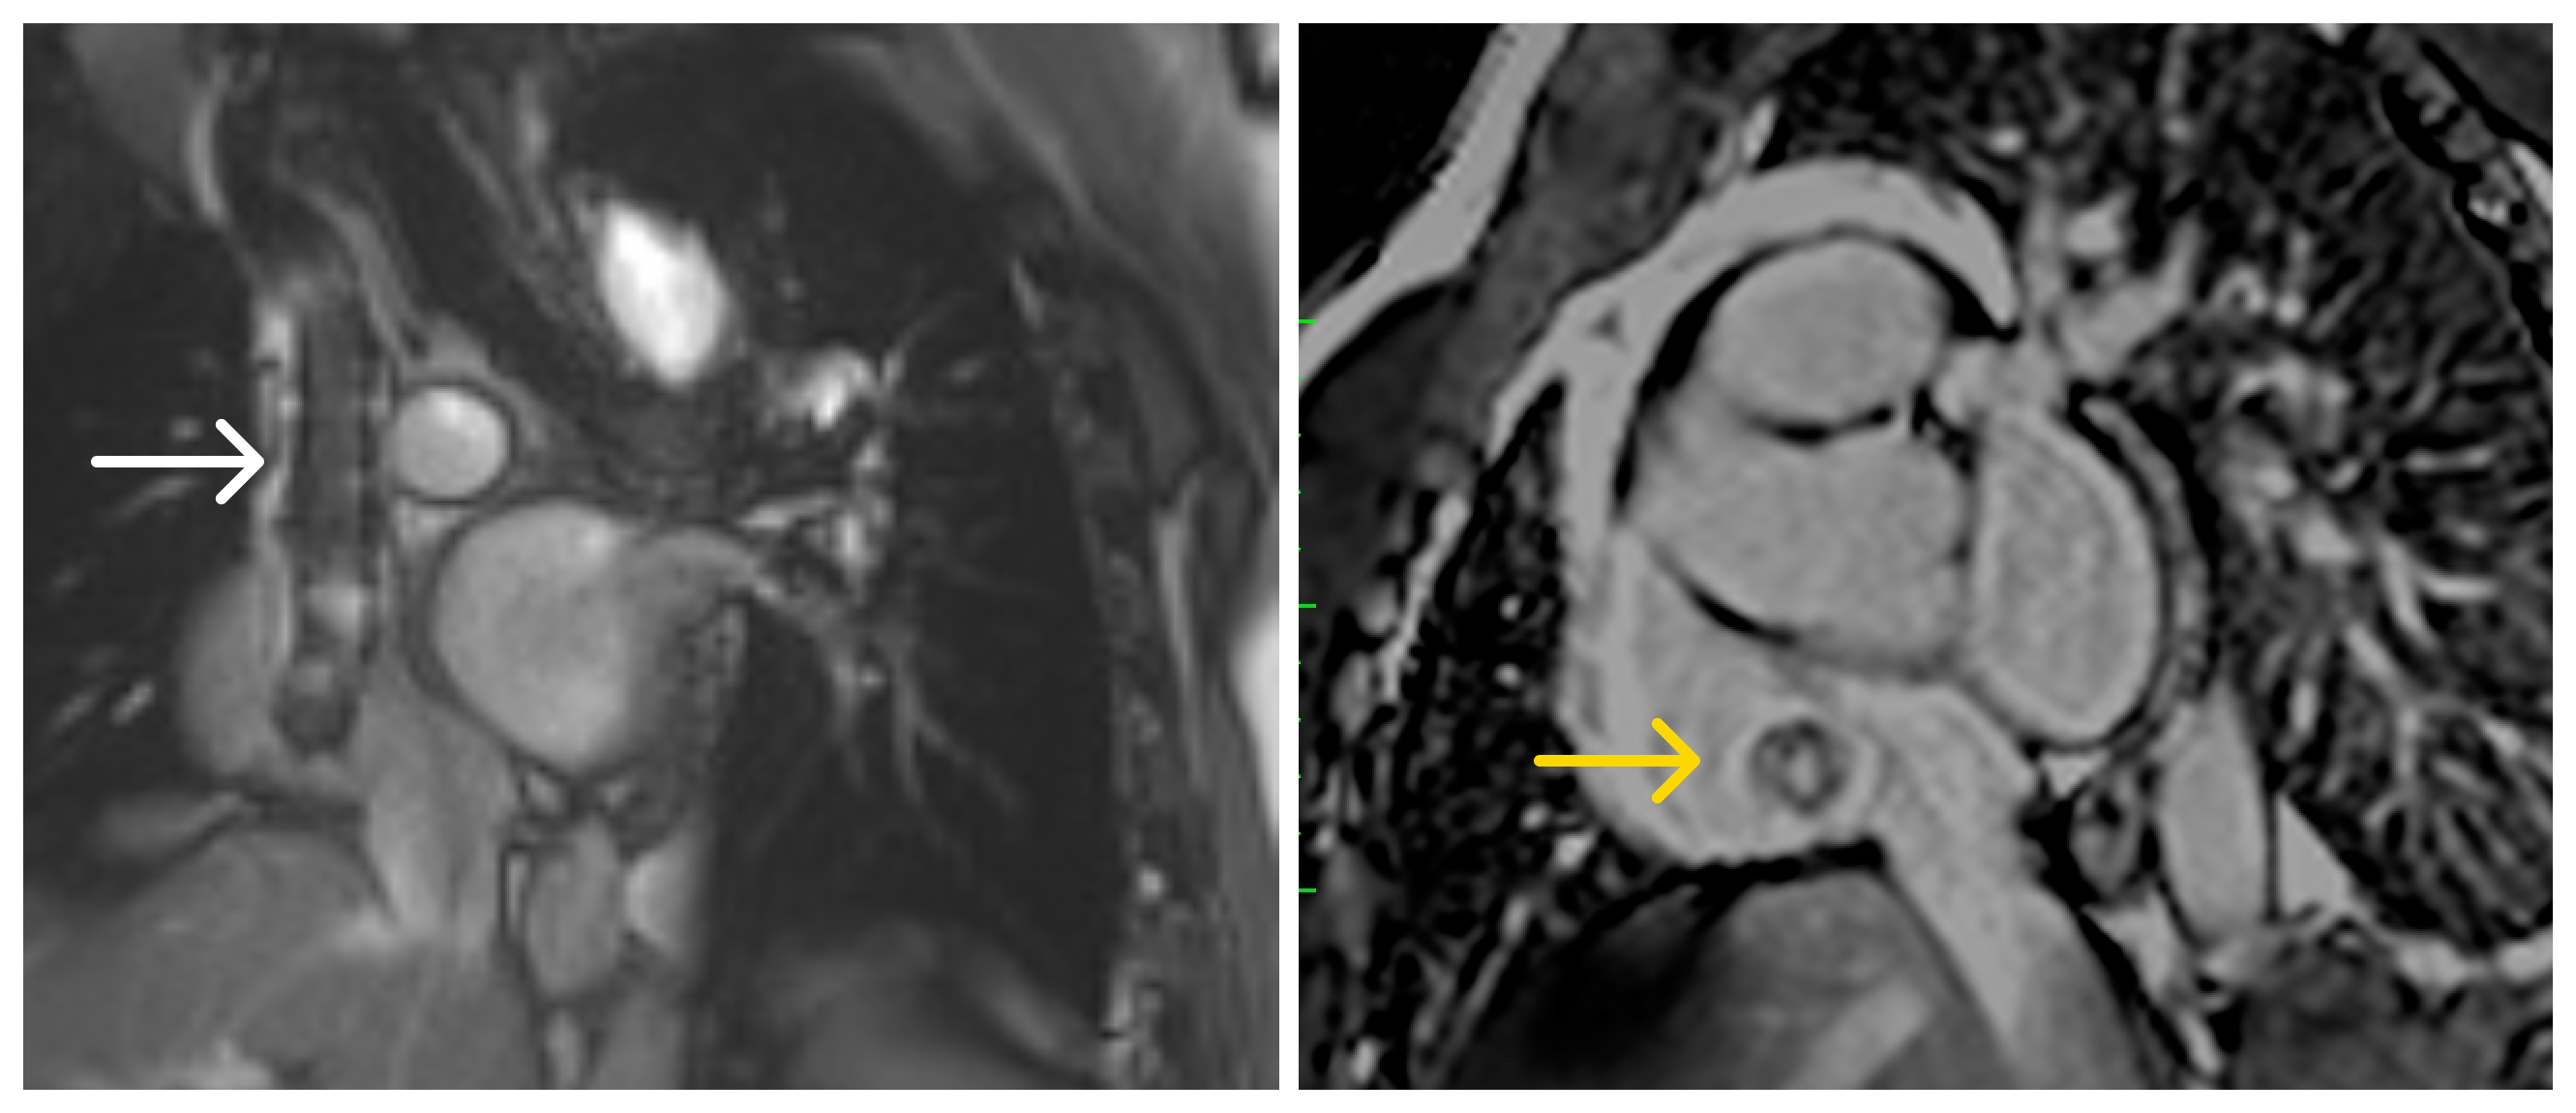

Image 2: Cardiac magnetic resonance. Left: tubular structure in the SVC with susceptibility artifact extending into the RA (white arrow). Right: single-shot LGE PSIR demonstrating contrast opacification within the stent lumen, consistent with preserved flow (yellow arrow).